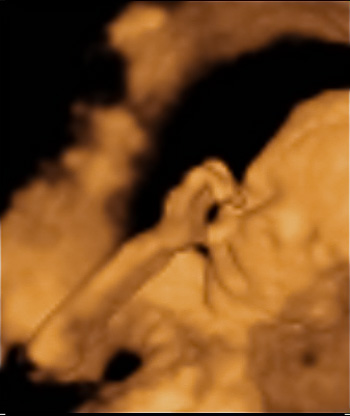

Anna kislányunk a Mester utcában készült fotón. Nagyon jó kép

natalia2

Hát ezek a képek írtó cukik.

Nagyon aranyos kislányod van. Ilyen tökéletes képet még festeni sem lehetne. Nekünk még hasonló sem sikerült, ezért irigykedem :lol: